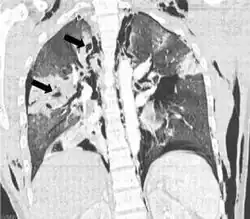

| Coronal CT scan showing lucencies (pale areas in radiography) in the lung caused by pulmonary lacerations on the left of the image (black arrows) | |